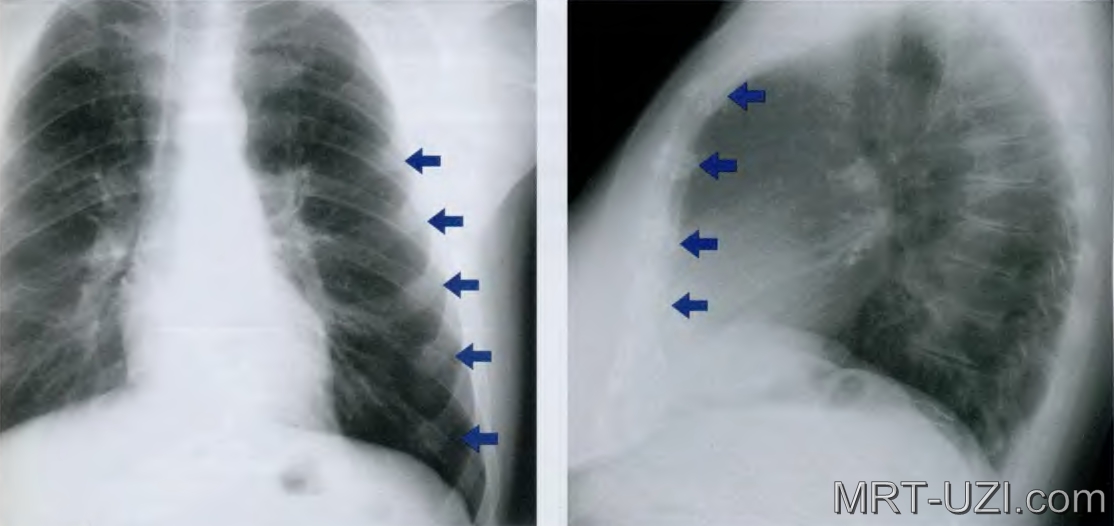

«Затемнение в легком» на рентгенограмме

Рентгенография – основной инструмент при диагностике заболеваний органов дыхательной системы и грудной полости в целом. Этот метод представляет собой.

получения изображения на пленку с помощью рентгеновских лучей. В зависимости от того какие среды проходят лучи, на рентгенологическом снимке видны участки затемнения или просветления в легочной ткани. Предположить клинический диагноз врачу-рентгенологу помогает много различных нюансов: размер затемнения, его локализация, форма и другое.

Симптом затемнения может быть внутрилегочной , когда причина находится непосредственно в легочной ткани, и внелегочной, когда причина где-то за ее пределами.

Внутрилегочное затемнение отличается по размерам, по количеству, по интенсивности, по четкости контуров. Обнаруживается в случае:

- уплотнения ткани легкого, обусловленного воспалительным процессом

- опухолевого процесса (роста узла опухоли)

- спадение легкого (наличия безвоздушного участка легкого)

- туберкулезного процесса в легких

Внелегочное затемнение – это симптом, который обусловлен проблемами не связанными с легкими. Как это не удивительно, но на рентгенограмме легких проецируются еще многие другие органы. Такие затемнения могут обнаруживаться в случае:

- наличия жидкости (крови, экссудата и др.) в плевральной полости

Рентгенограмма. Очаговая пневмония в нижней доле справа

Белое пятно при воспалении легких имеет нечеткие размытые контуры. Интенсивность его может быть низкой или высокой, что зависит от особенностей экссудата (воспалительной жидкости в просвете альвеол). К месту его локализации подходит дорожка от корня за счет лимфангита.